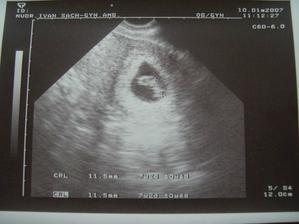

SRPŇÁTKA 2007 - fotky UTZ

album věnované mimískům, které se narodí v srpnu 2007 a jejich maminkám ze "Společného termínu SRPEN"